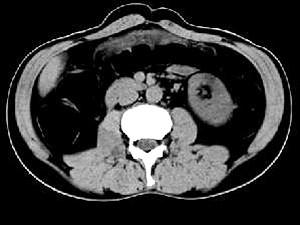

问题 女,51岁,腹胀、腹痛、进行性消瘦,影像检查如下图,最佳诊断是 ( )

选项 A、乙状结肠淋巴瘤 B、乙状结肠息肉 C、乙状结肠结核 D、乙状结肠癌 E、乙状结肠crohn病

答案 D